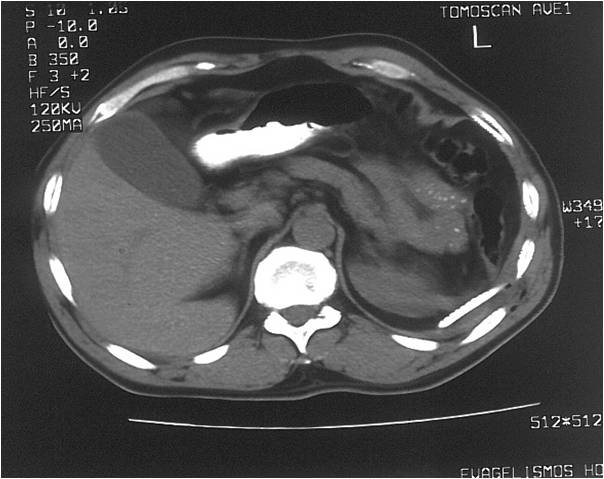

- Abscess post left hemicolectomy

- Successful placement and drainage